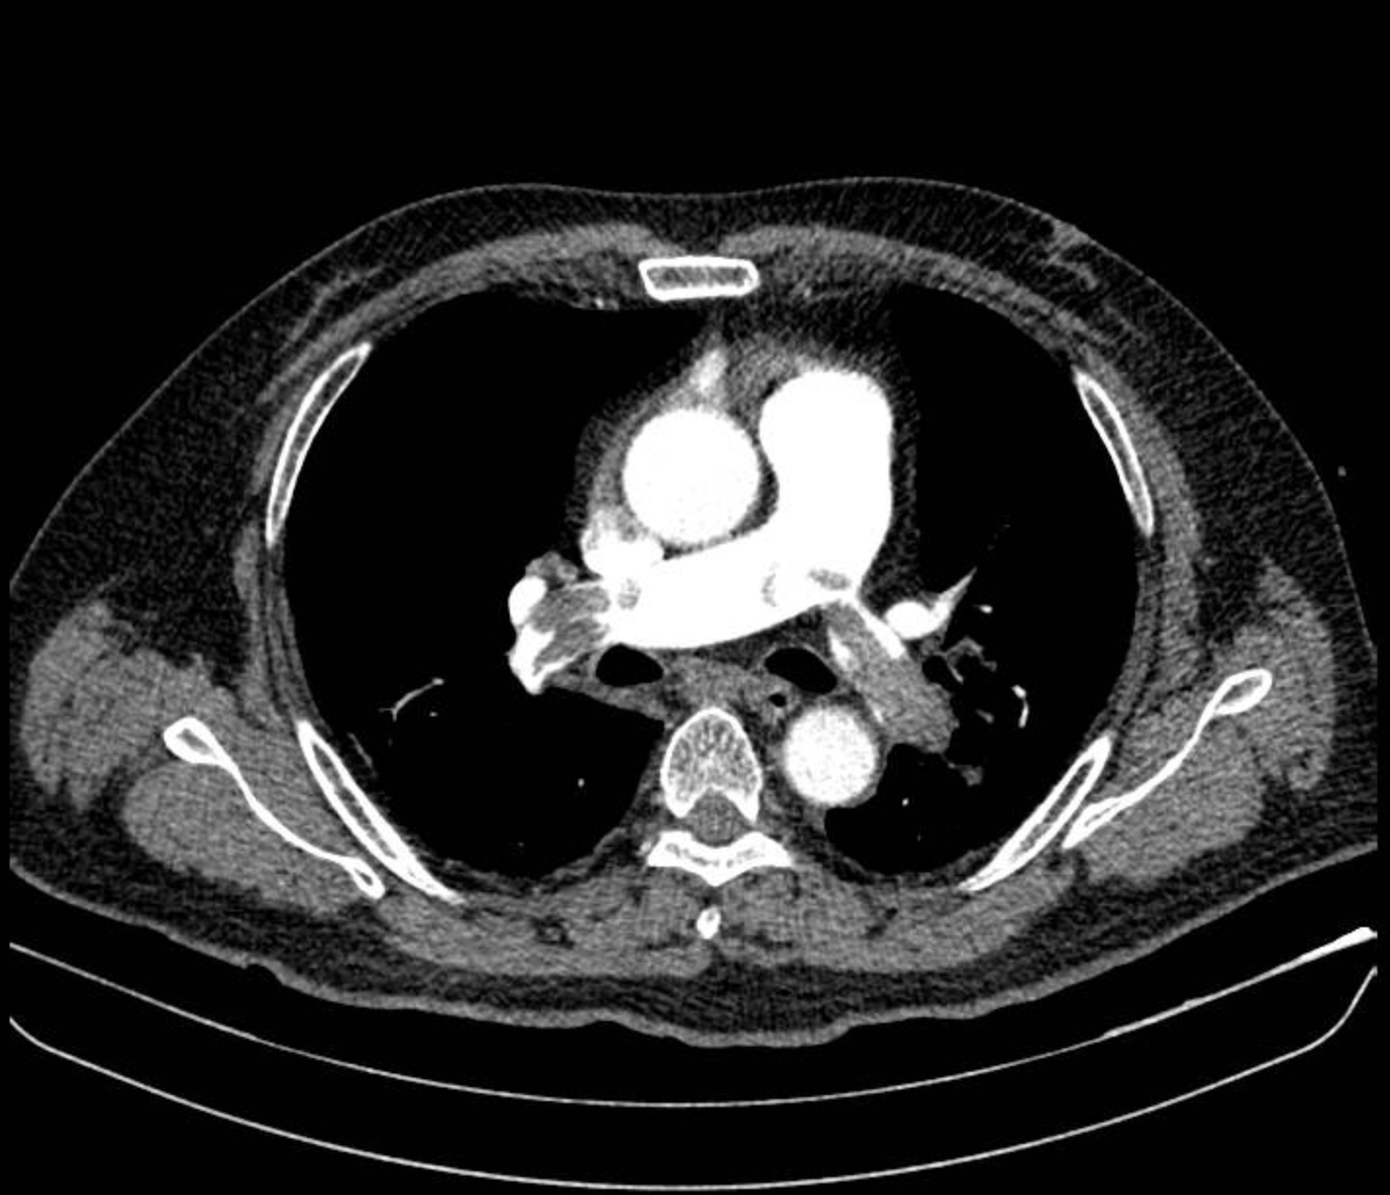

Hình ảnh chụp CT mạch máu phổi cho thấy huyết khối lớn bít tắc động mạch phổi hai bên (ảnh: BVCC)

Nhận định đây là trường hợp sốc tắc nghẽn do thuyên tắc phổi, ê kíp bác sĩ đã nhanh chóng dùng thuốc vận mạch để nâng huyết áp, đồng thời chuyển người bệnh đi chụp cắt lớp vi tính (CT) mạch máu phổi. Hình ảnh ghi nhận huyết khối lớn bít tắc hai nhánh động mạch phổi – nguyên nhân khiến tim phải “gồng” hết sức để bơm máu qua đoạn mạch bị tắc.